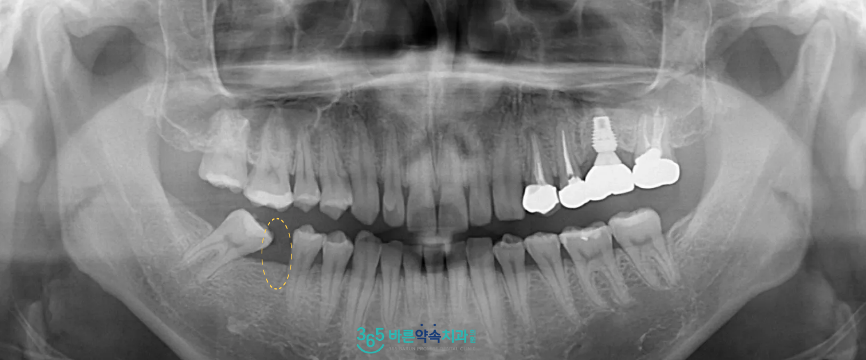

정밀한 상담을 위해

파노라마 사진을 촬영해 보았더니

아래턱 오른쪽 첫 번째 큰 어금니(#46)가

상실되어

상실된 빈 공간으로

바로 뒤의 두 번째 큰 어금니(#47)가

기울어져 있는 상태였으며,

맞물리는

오른쪽 위턱 첫 번째 큰 어금니(#16)가

아래로 솟구쳐 내려와 있었는데요.

상실된 부위에 임플란트를 식립하기에는

공간이 부족한 상태로